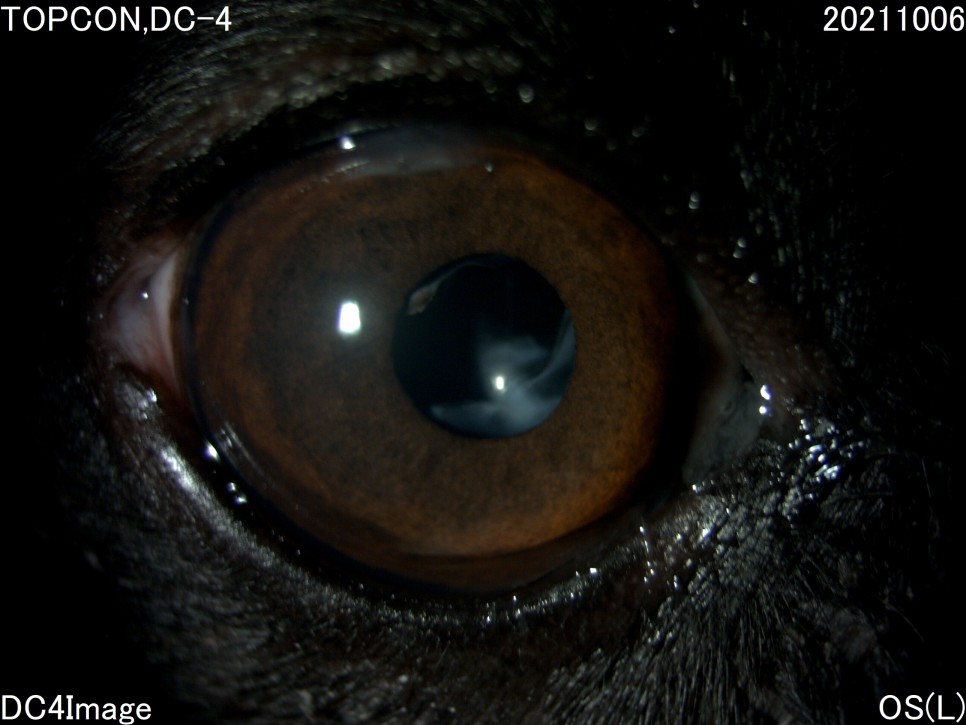

- 세극등 현미경 검사

양안의 백내장이 심하게 진행되고 있었지만 다행히도 당뇨병 관리를 하고 있는 전주 24시 동물병원은 당뇨병 관리 뿐만 아니라 눈 관리도 계속해 주셨기 때문에 내원 당시에는 양안 모두 심한 포도막염은 없었습니다.

그러나 왼쪽 눈은 백내장 단계 중 4기인 과성숙 단계로 진행되었으며, 이전에 앓고 있던 심한 포도막염에 의해 홍채의 일부가 수정체에 유착되어 있는 것이 보였습니다.